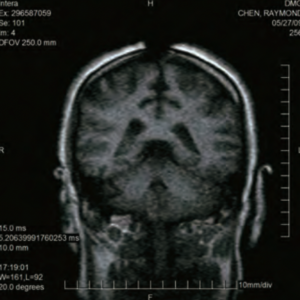

佛教弟子侯欲善,數年前罹患肺癌,因長期接受化學治療而深感痛苦不堪,甚至有痛不欲生的感覺。約在一年半以前,他到義雲高國際文化基金會聽聞義雲高大師的佛法開示法音帶,當時他對義大師所闡示的精妙佛法感到非常震驚,便對大師產生無限敬仰,從此全心投入基金會共修,對義大師的開示法音從不缺席,並發心到基金會做全天候義工。

侯欲善自此精進勤修佛法,很快就深入境界,他身上的癌症病痛也突然消失,連醫院所開的嗎啡止痛針都用不上。